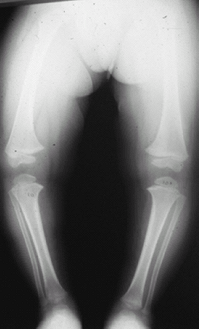

Fig.

3. This 2-year-old patient had bowed legs. The metaphyseal–diaphyseal

angle is 10° on each side. The bowing is more pronounced on the femoral

than the tibial metaphysis. It resolved without treatment.